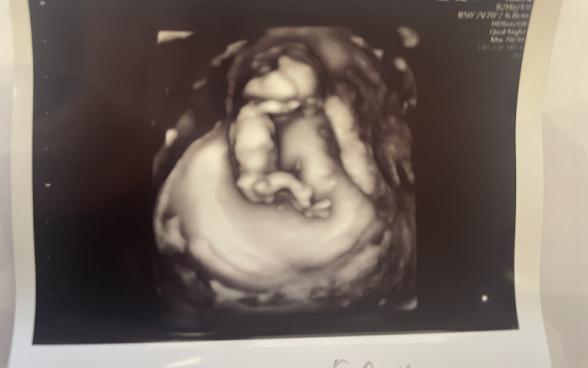

12週2日の時点で検診を受けた際のエコー写真で、胎児の頭の形が凹んでいるように見えて気になっています。

またエコー写真で後頭部〜首の後ろに暗い部分(=むくみ)があるとダウン症の傾向があるとネットで見てから、自分のエコー写真がそうではないか?と更に不安になってしまいました。

検診時に頭が凹んでいることを聞けず、先生からはエコーについて特に何も言われなかったです。ただ、その場でNIPTを検討していることを先生と会話したのでもしその傾向があれば指摘されてるはずだとは思いつつ、やはり不安になりこちらで相談させていただきました。

3D,4Dエコーの場合には、お子さんを立体的に映して見るものなので、超音波の当たる向きや位置などによって、影になる部分が出てきます。そのために穴が空いているように見えたり、影になっているところが凹んで見えたりするのかもしれませんね。ですが、医師から何も指摘がなかったということであれば、ご心配はないように思いますよ。何か異常があれば、医師は必ずママさんにお話しすると思いますし、特に問題の指摘がなければ、安心していただいて大丈夫だと思いますよ。